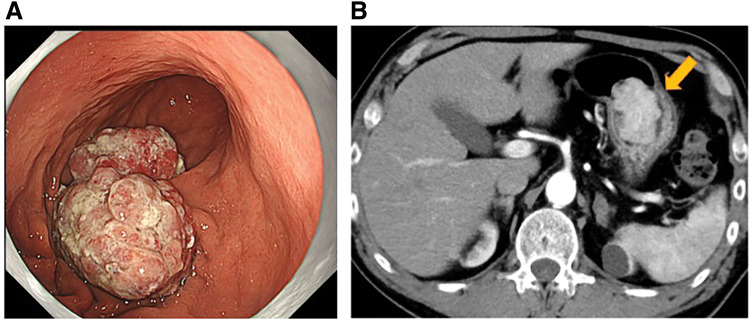

Case presentation: A 69-year-old man with a 30-mm tumor arising from the posterior wall of the gastric body was scheduled for elective surgery. During hospitalization for diabetes mellitus management, he developed sudden epigastric pain and nausea. Upper gastrointestinal endoscopy revealed tumor prolapse into the duodenum, leading to a diagnosis of ball valve syndrome. After successful endoscopic reduction, open local gastrectomy was performed. Pathological examination confirmed a well-differentiated tubular adenocarcinoma, classified as pT1b (SM2) N0M0, pStage IA.